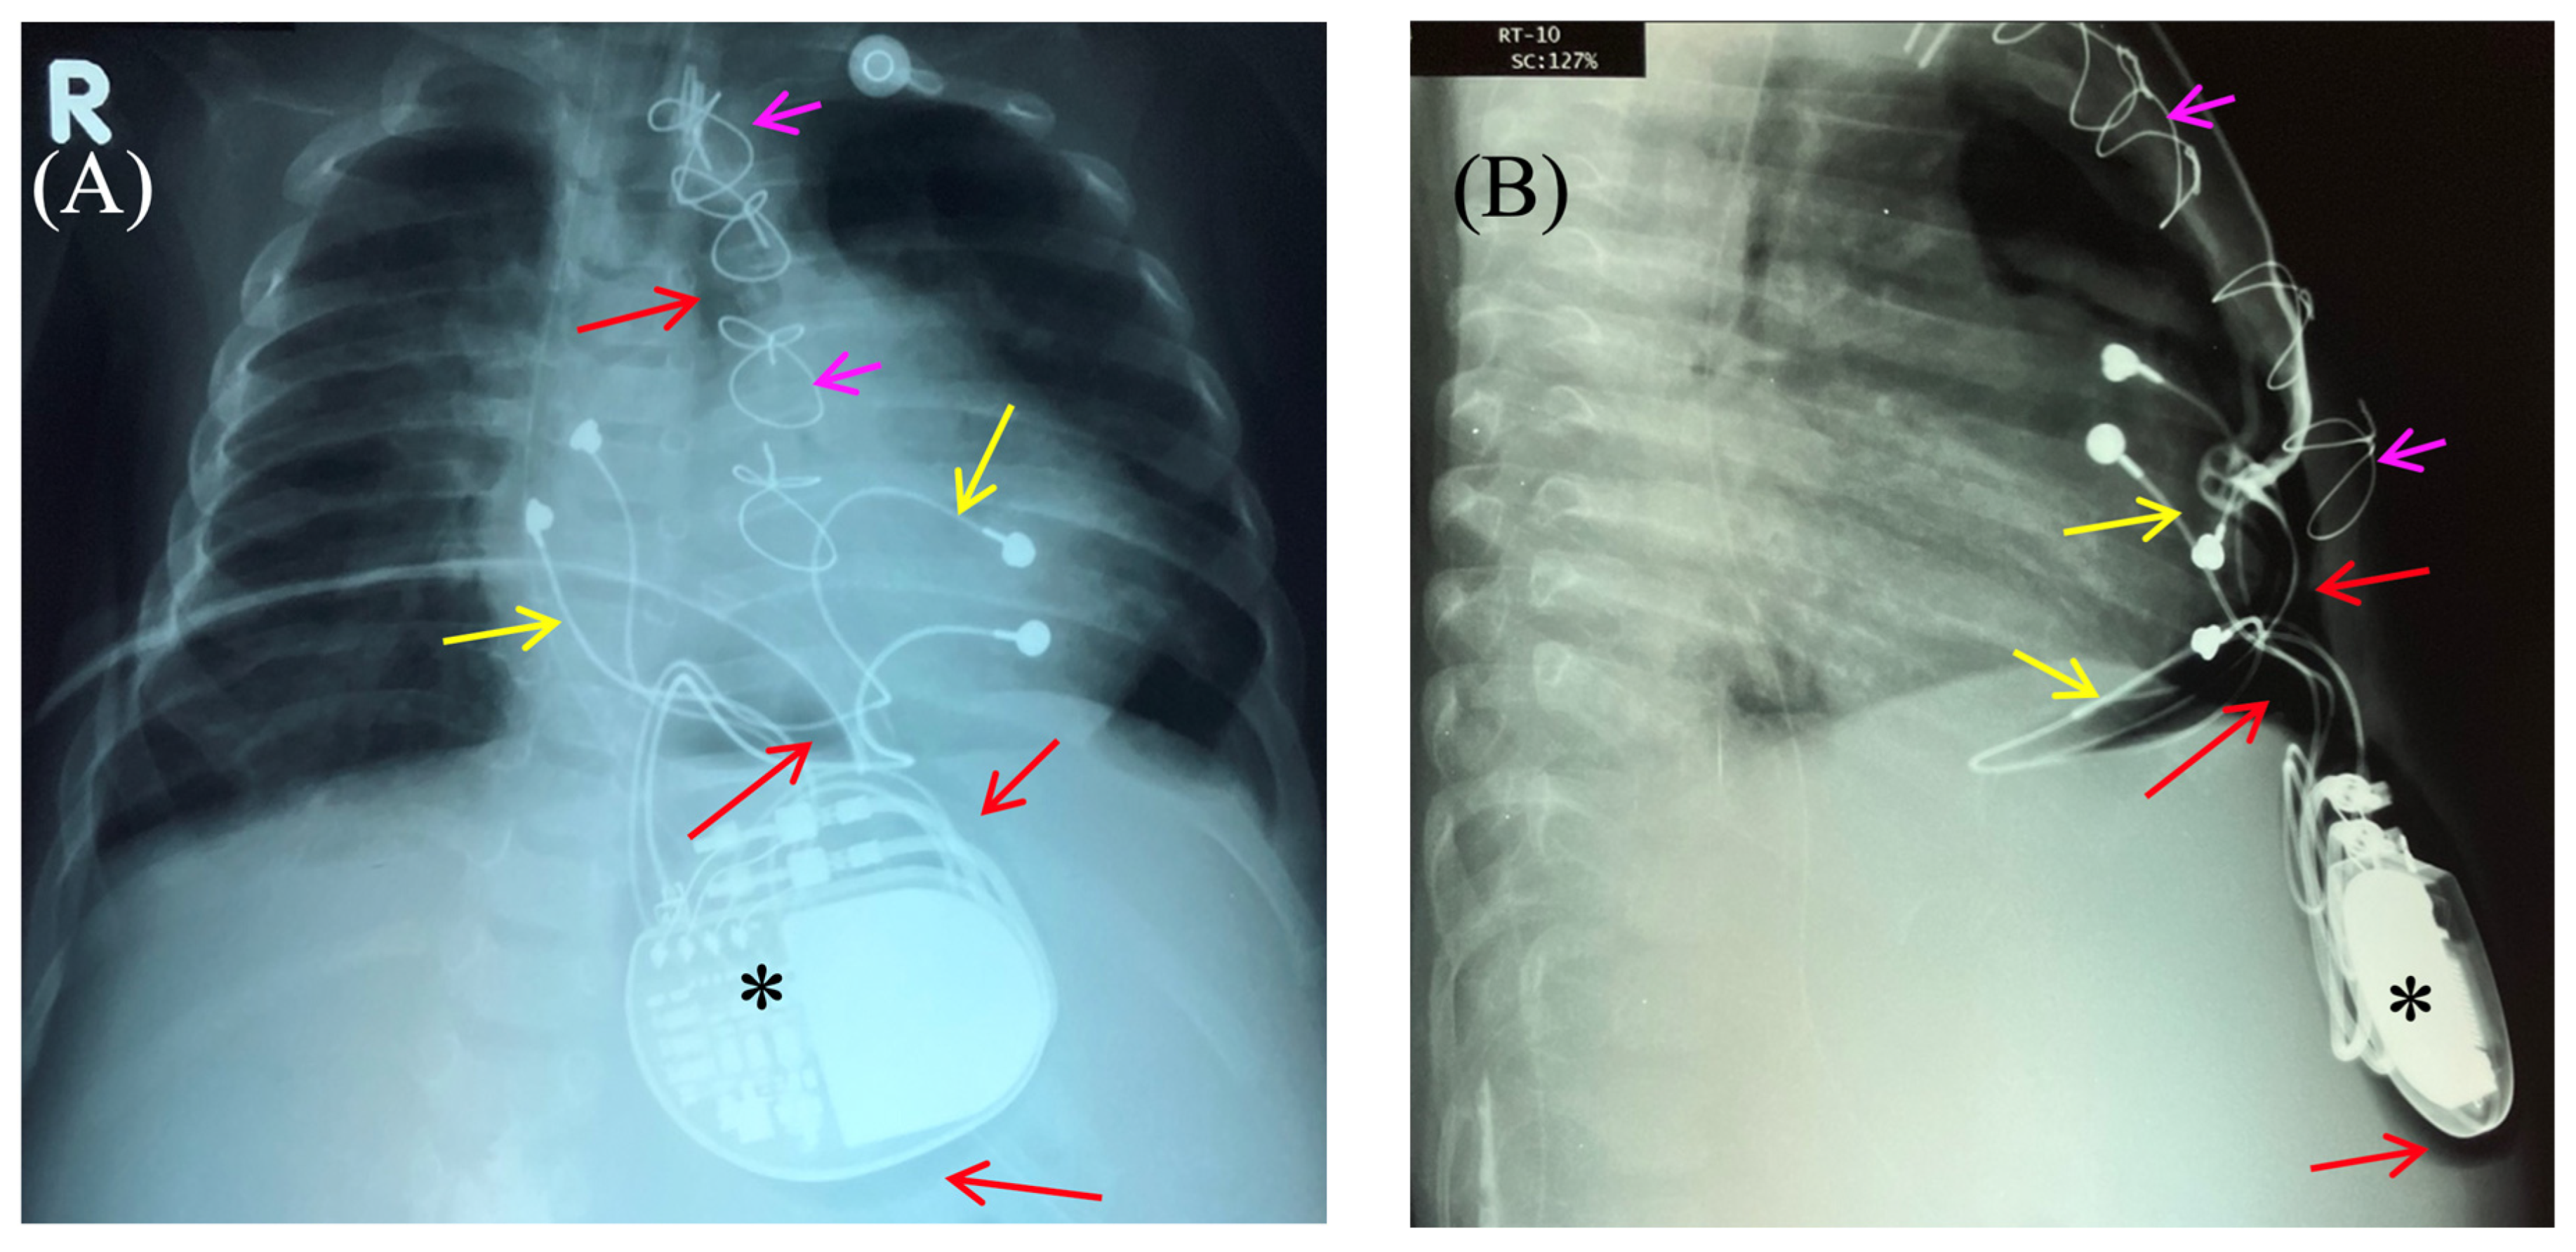

Based on the results of three wound cultures, no pathogenic flora were detected. On the seventh day, the wound was sutured, and healing proceeded without complications. The wound healed seven days after suture closure. A follow-up chest and abdominal X-ray revealed no signs of pneumothorax, pneumomediastinum, or free air in the upper anterior abdominal wall along the midline in the projection of the pacemaker pocket (Figure 6).

Figure 6. Chest X-ray after surgery debridement and closure of the wound. Chest X-ray (frontal (A) and lateral (B) view) shows no signs of pneumothorax, pneumopericardium, pneumomediastinum with minimal air at the pacemaker pocket site. (C) The healed sternotomy and the projection of the pacemaker pocket 12 days after revision and sanitation.